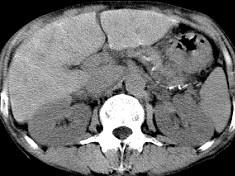

问题 男,40岁有血吸虫感染史,腹胀不适,食欲减退,CT扫描所见如图,最可能的诊断是 ( )

选项 A.肝炎后肝硬化 B.血吸虫后肝硬化 C.酒精性肝硬化 D.胆汁性肝硬化 E.脂肪肝

答案 B